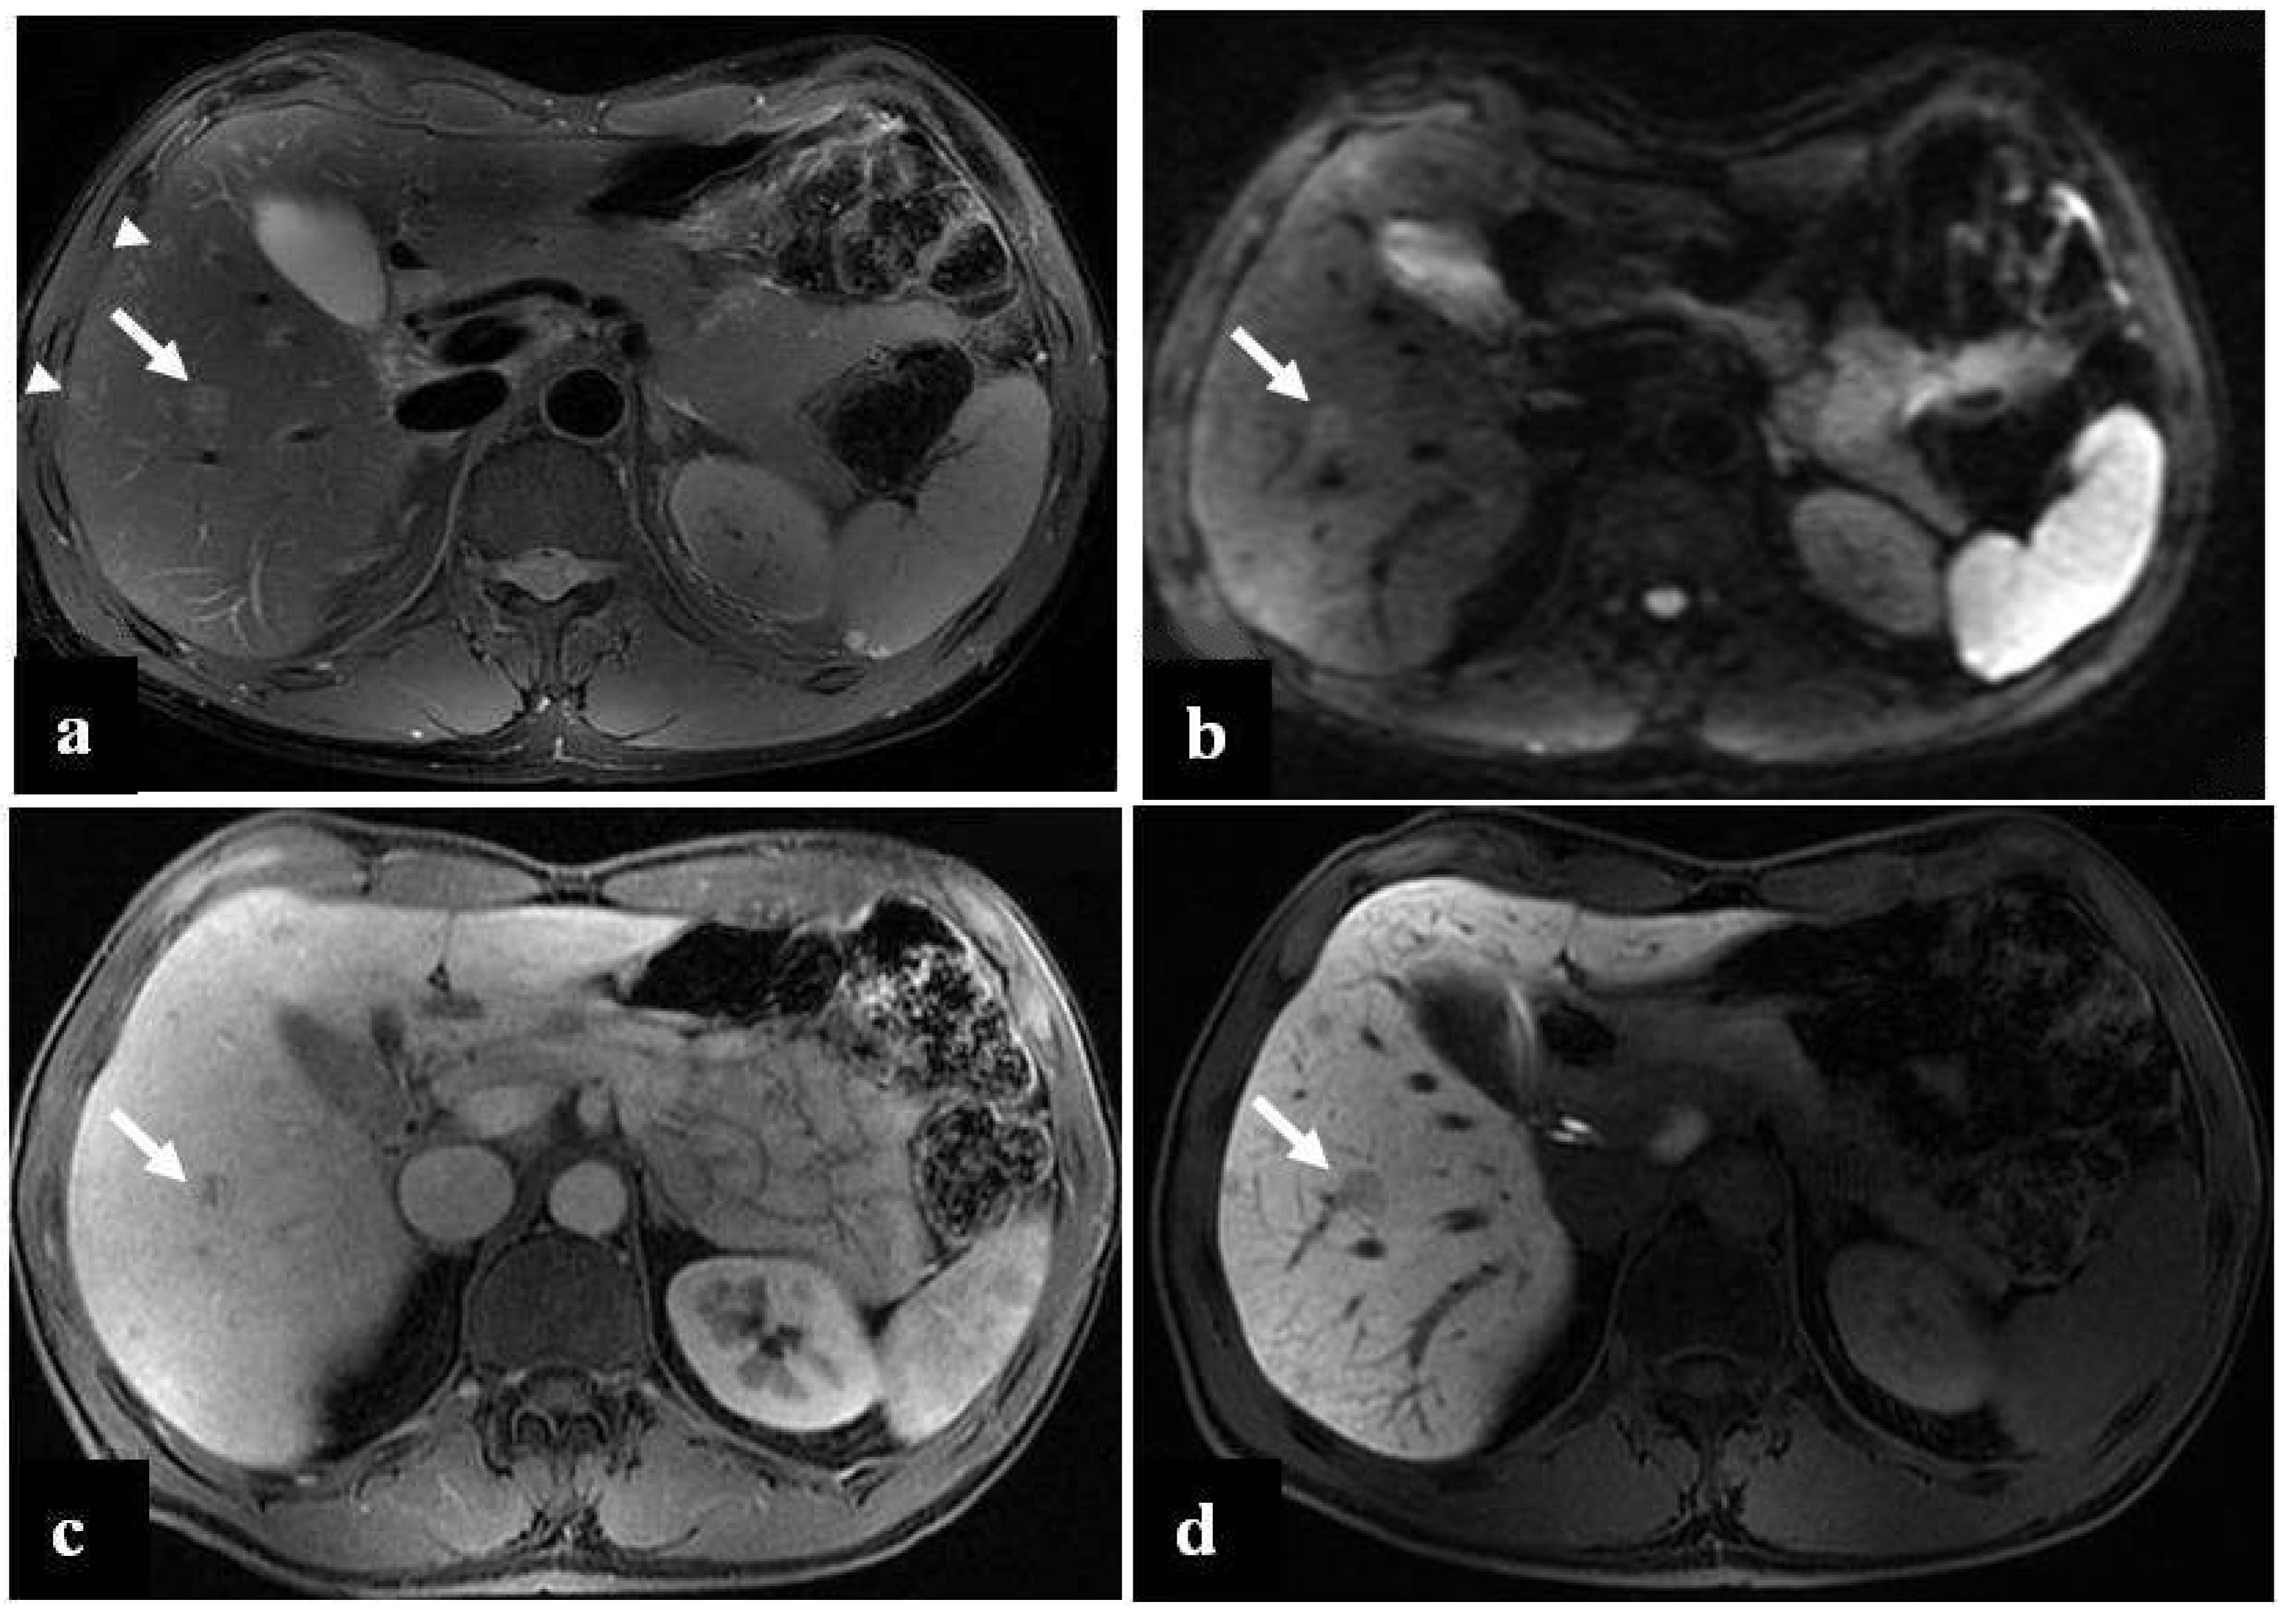

- Furlan, A.; Brancatelli, G.; Dioguardi Burgio, M.; Grazioli, L.; Lee, J.M.; Murmura, E.; Lucidarme, O.; Strauss, C.; Rode, A.; Ronot, M.; et al. Focal Nodular Hyperplasia After Treatment With Oxaliplatin: A Multiinstitutional Series of Cases Diagnosed at MRI. AJR Am. J. Roentgenol. 2018, 210, 775–779. [Google Scholar] [CrossRef]

- Yoneda, N.; Matsui, O.; Kitao, A.; Kozaka, K.; Kobayashi, S.; Sasaki, M.; Yoshida, K.; Inoue, D.; Minami, T.; Gabata, T. Benign hepatocellular nodules: Hepatobiliary phase of gadoxetic acid–enhanced MR imaging based on molecular background. Radiographics 2016, 36, 2010–2027. [Google Scholar] [CrossRef]

- McInnes, M.D.; Hibbert, R.M.; Inacio, J.R.; Schieda, N. Focal nodular hyperplasia and hepatocellular adenoma: Accuracy of gadoxetic acid–enhanced MR imaging—A systematic review. Radiology 2015, 277, 413–423. [Google Scholar] [CrossRef]